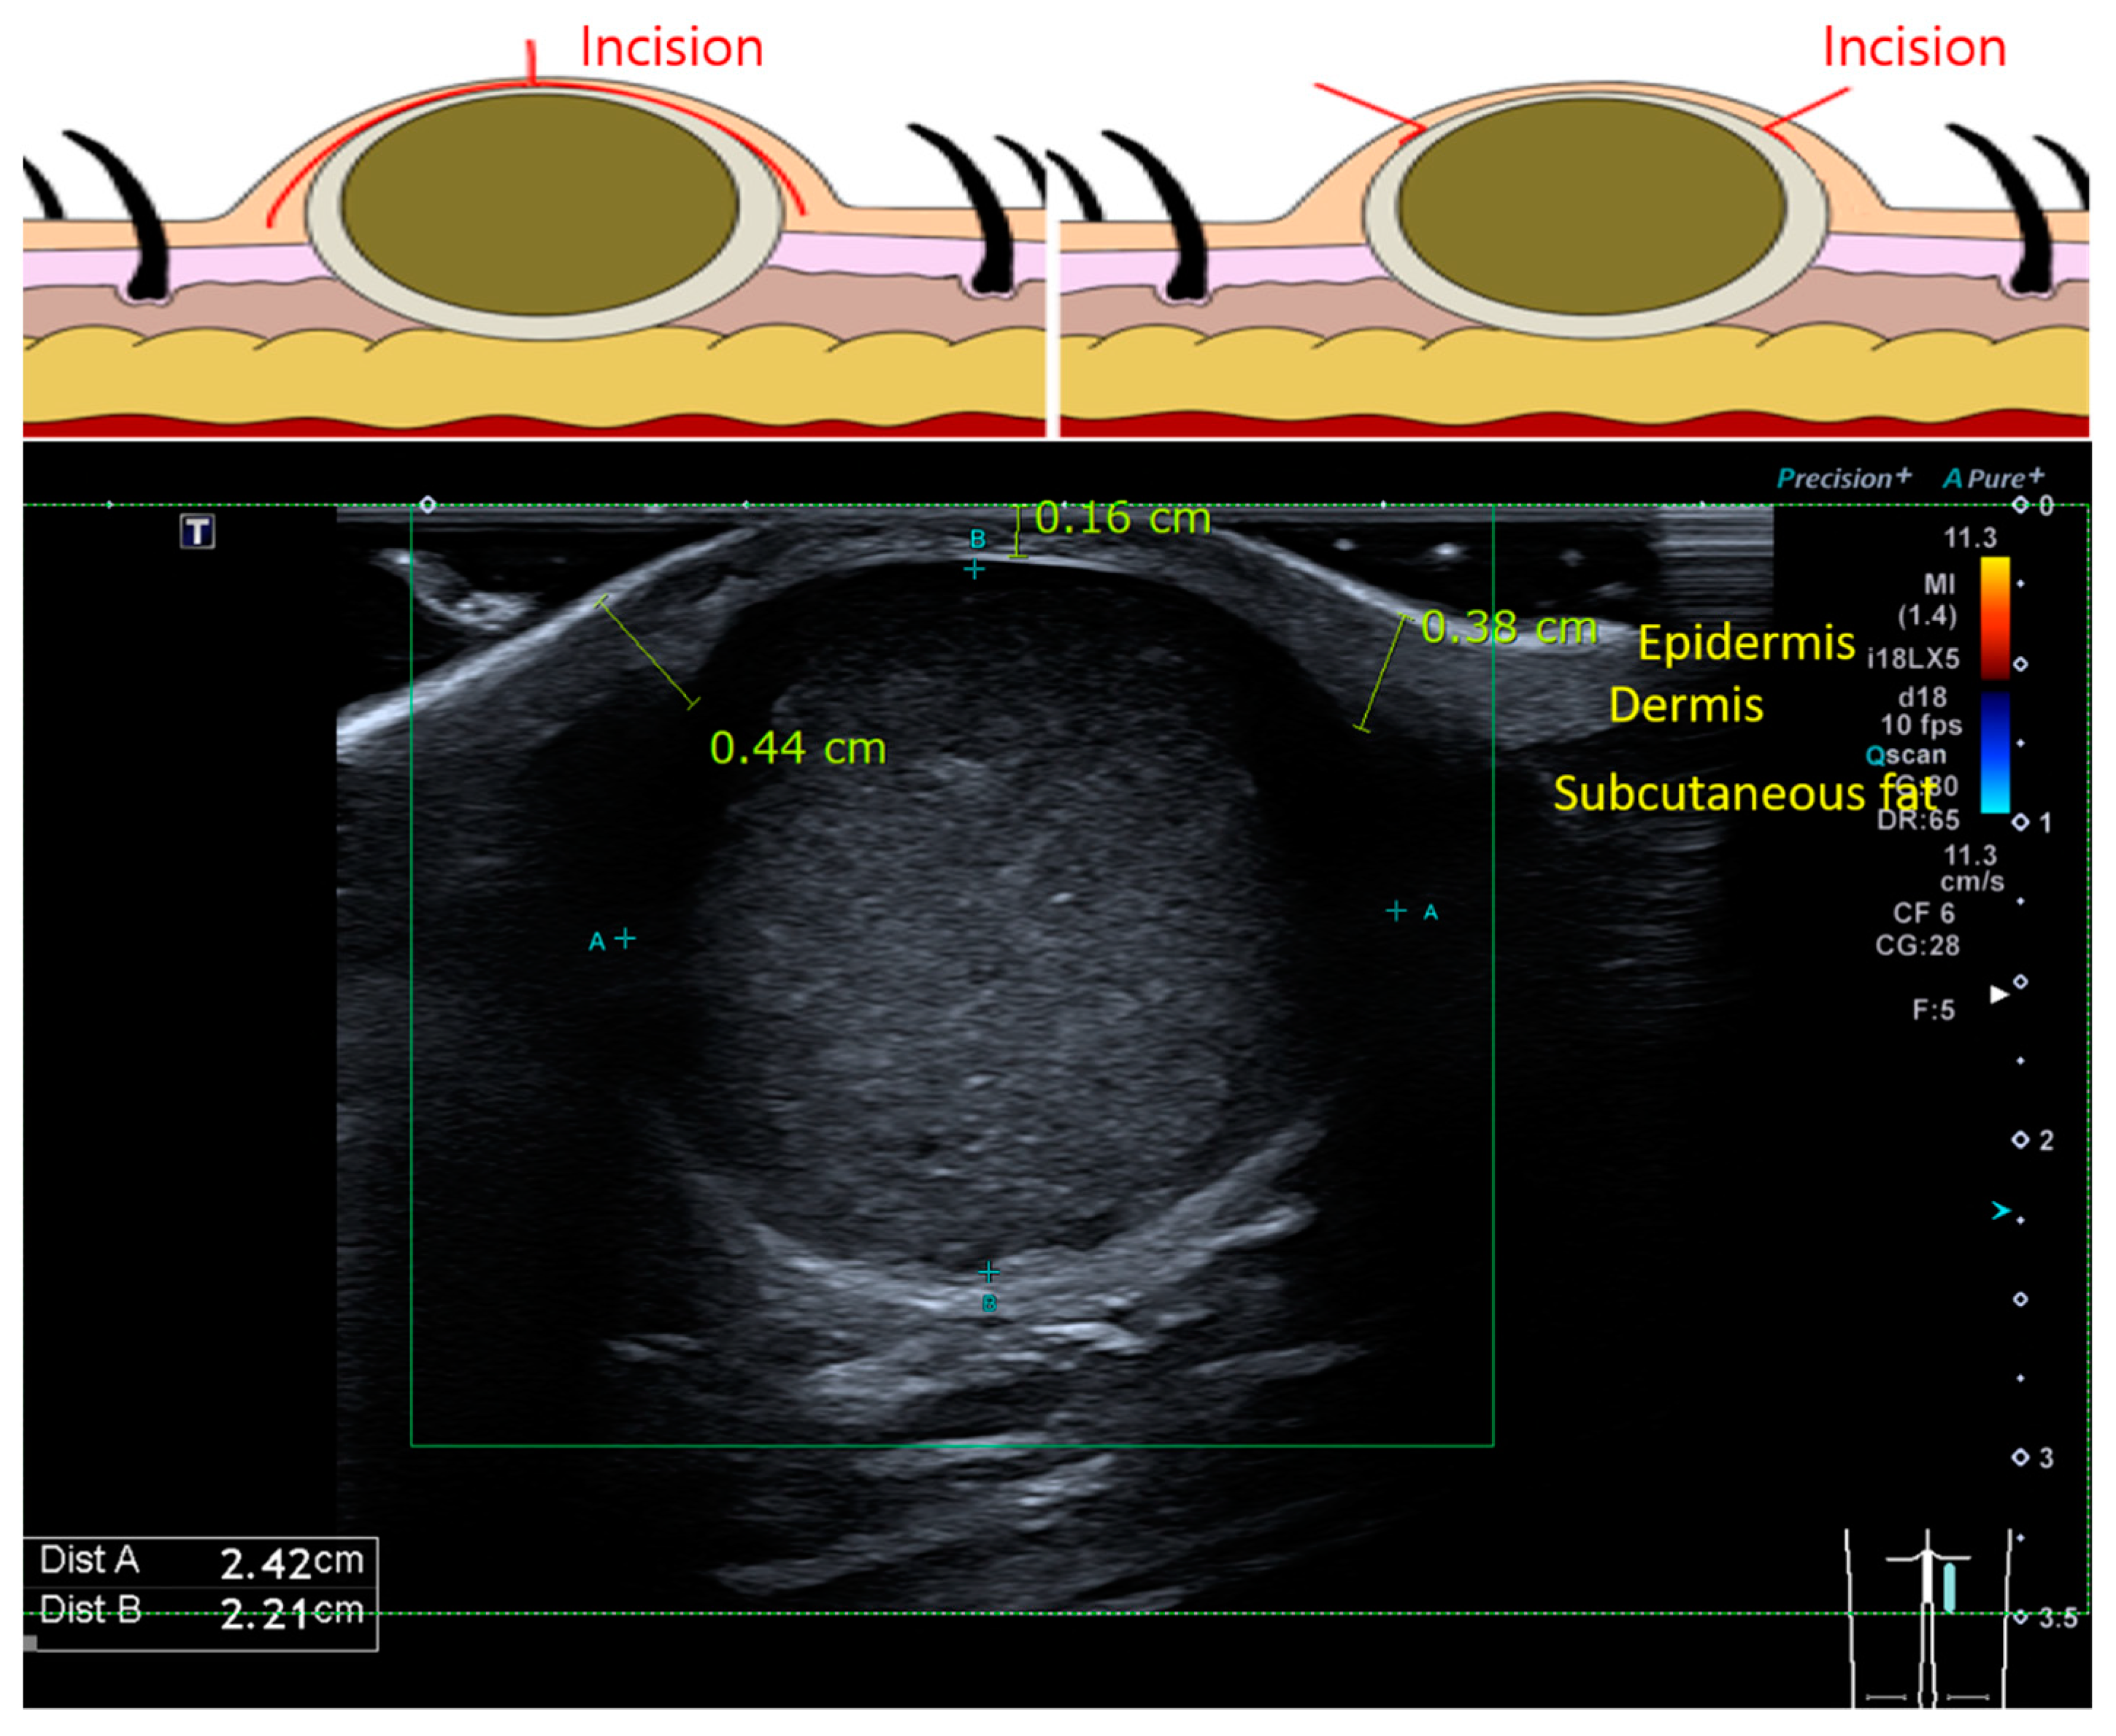

2.1. Patient Selection and Surgical Methods